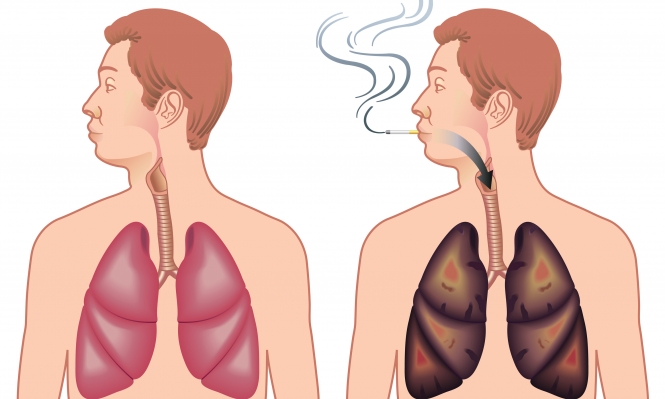

الرئة السوداء مرض صامت يسبب الإعاقة أو الوفاة اليوم السابع

التخلص من سموم الرئتين بعد الإقلاع عن التدخين صحة عرب 48

طريقة بسيطة لتنظيف الرئتين من النيكوتين البيان الصحي الأخيرة البيان

أفضل مشروب طبيعي يطه ر الرئتين من آثار التدخين قناة العالم الاخبارية